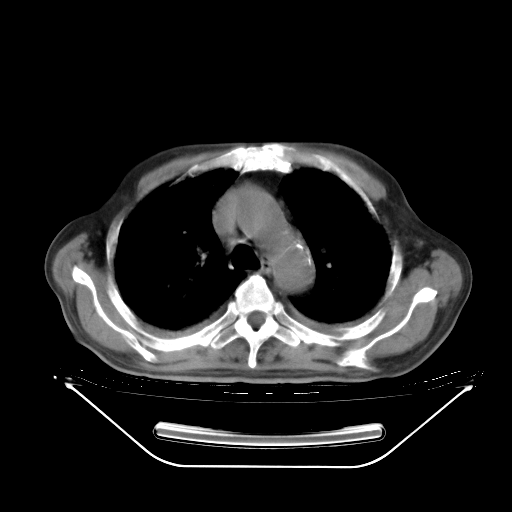

今天复查肺部CT,发现双肺广泛磨玻璃样改变。所以我把3月19日和5月9日相隔50天的肺部CT上传。请大家会诊。

2009年3月19日肺部CT片。

2009年3月19日肺部CT